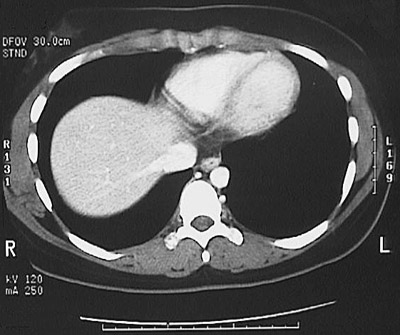

[T10] This is a normal abdominal CT scan with contrast demonstrating the lower chest with the left ventricle and right ventricle and interventricular septum and inferior vena cava and right lung and left lung and liver and esophagus and aorta .